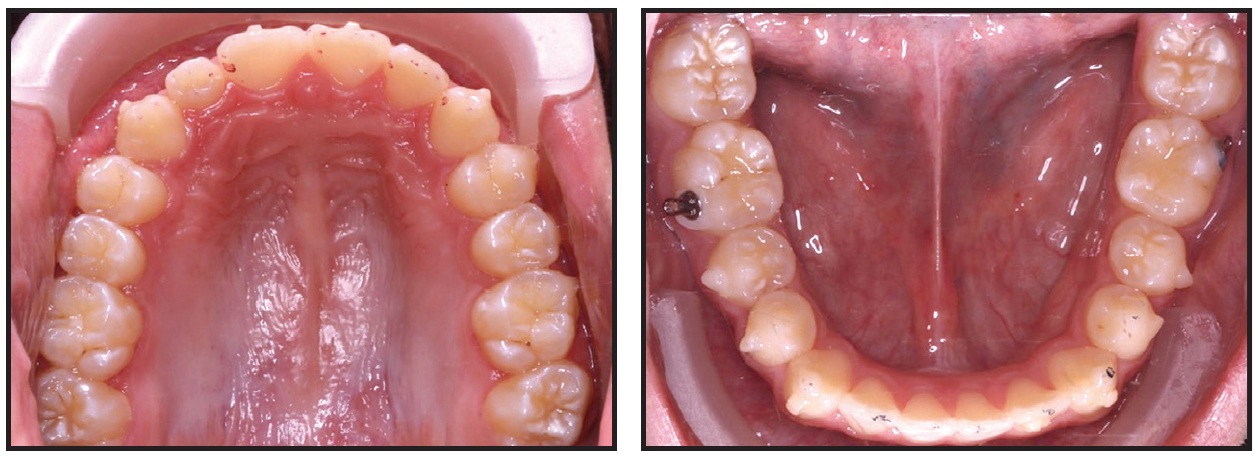

This 10-year-old female presented with upper crowding and protrusive lower incisors (Fig. 13). The upper first premolars were extracted to relieve the crowding, but no extractions were performed in the lower arch.

Fig. 13 10-year-old female patient with upper crowding and protrusive lower incisors before treatment.

As a result, the lower incisors were further proclined, and we ran out of overjet trying to close the upper spaces (Fig. 14).

Fig. 14 After upper first-premolar extractions and 15 months of treatment, lower incisors further proclined, with insufficient overjet for upper space closure.

We had to extract the lower left first premolar to shift the lower midline and upright the lower incisors enough to permit the upper space closure.

The lesson here is to keep the lower incisors upright. In an asymmetrical Class II case, that might call for a three-premolar extraction pattern. In this particular patient, it also helped with the alignment and allowed complete eruption of the lower left second molar (Fig. 15).

Fig. 15 Patient after 25 months of treatment, following extraction of lower left first premolar to allow uprighting of lower incisors.